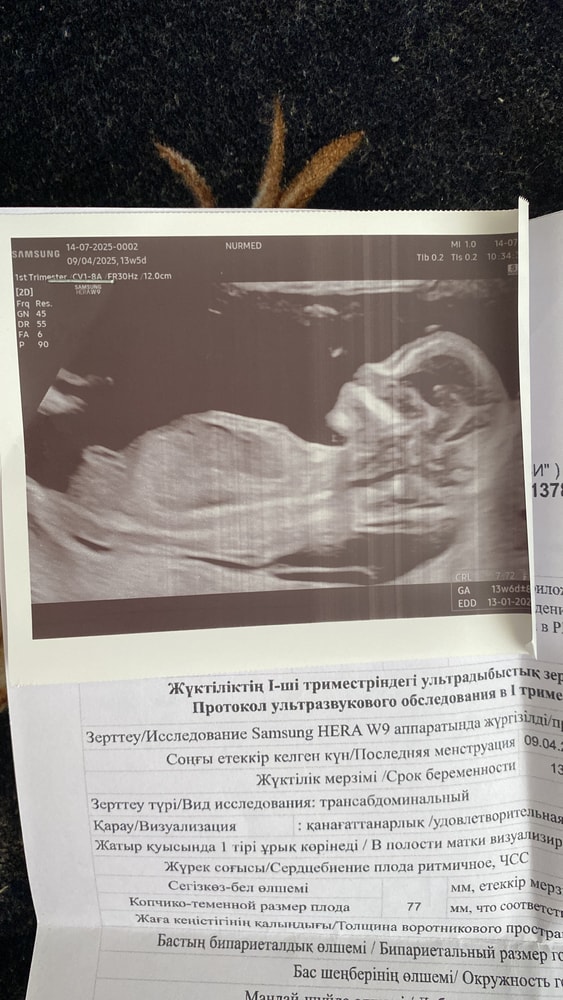

Кого видите?девочку или мальчика 😁

Я за мальчика, но это гадание) У младшего сына тоже был бугорок вниз. Я думала, что девочка. Но узист уже в 12 недель сказал, что похоже на мальчика. Не ошибся)

Аня, бугорок параллелен к позвонку,в противном случае только мальчик)у меня первый вариант

Аня, вы может на втором снимке увидели мальчика,там да похож на мальчика ,а тут свежее сегодняшнее)

asel, здесь на мальчика похоже) но лучше попозже еще раз посмотреть.

Аиша Оразова, а не наоборот?😁 тут же виден пирожочек а не мальчиковый стручок

asel, пирожочек будет виден после 16 недели, а это половой бугорок . Пусть будет здоровая доченька у вас 🫂🩷

asel, ну бугорог вроде параллельно позвонку, похоже на девочку)

Eseniya , вчера девочку предположила узистка по бугорку,но говорит у некоторых мальчиков тоже лежит как у девки😂

Деля , блин я вас не понимаю вы на какой снимок отвечаете?😁первый снимок это сегодняшний там нет ничего мальчиковского)а на втором да на мальчика похож )это неделю назад было